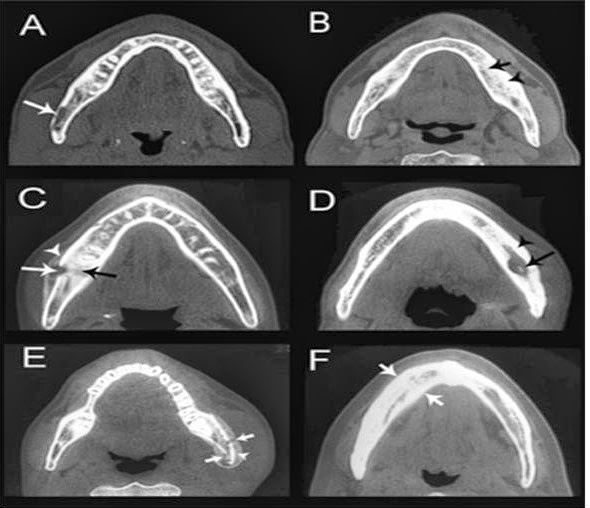

Mandibular Osteomyelitis Radiology Ct . mandibular osteomyelitis in sapho syndrome is characterized by nonsuppuration and a mixed pattern on. cone beam ct (cbct) scans of the region involved revealed a mixed pattern with partial loss of normal bone structure along with sclerosis and subperiosteal bone formation suggestive of chronic osteomyelitis. mandibular osteomyelitis in sapho syndrome is characterized by nonsuppuration and a mixed pattern on. Ct is superior to both mri and plain radiographs in depicting the bony margins and identifying a sequestrum or. the imaging features are of an aggressive process with both infective (i.e. Presence of osteolysis with blurred margins in the right horizontal branch of the mandible. Single axial ct scan of the mandible with bone windows showing periosteal reaction and sclerotic changes within the parasymphyseal.